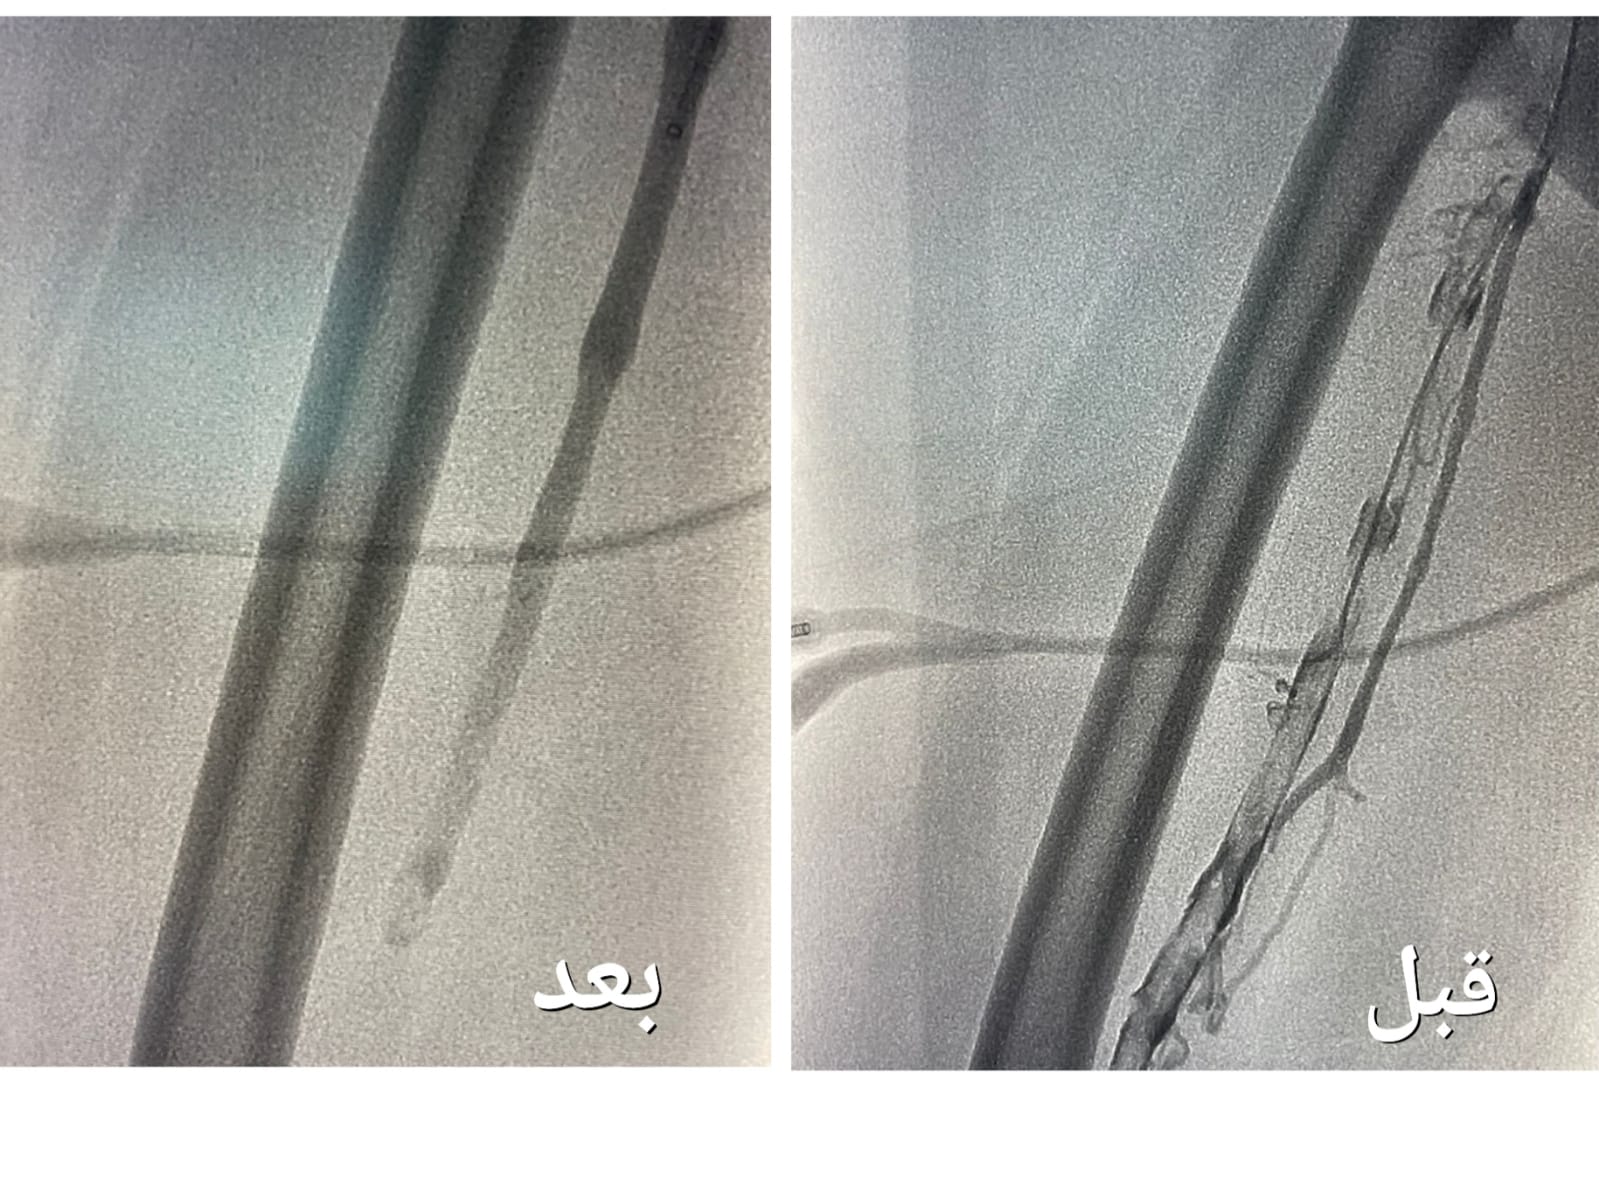

وأوضحت “الصحة” أنه بعد إجراء الفحوصات الطبية و الكشف تبين وجود جلطة وريدية من مستوى الكاحل إلى مستوى أوردة الحوض الأيمن ، و انسداد كامل في أوردة القدم اليمنى حتى الحوض ، قرر بعدها الفريق الطبي تنويم المريضة و التنسيق مع فريق وحدة الأشعة التداخلية بشكل عاجل لدراسة الحالة و معالجتها ، و وضع الخطة العلاجية ، لنقلها إلى غرف عمليات الأشعة لإجراء عملية بإستخدام جهاز إزالة الجلطات تحت التخدير الموضعي و التهدئة الواعية .

وقالت الوزارة إن العملية استغرقت نحو ساعتين ، تكللت _ ولله الحمد_ بالنجاح ، تم فيها تركيب فلتر للوريد الأجوف السفلي لمنع انتقال الجلطات للرئة ، و من ثم الدخول للوريد المتجلط في مستوى الكاحل و حقن مواد مذيبة للجلطات ، و قد استخدمت أجهزة نوعية لمثل هذه الحالات والتي تعمل على سحب الجلطات بعد إذابتها و توسعة الأوردة بالبالون لإعادة جريان الدم .